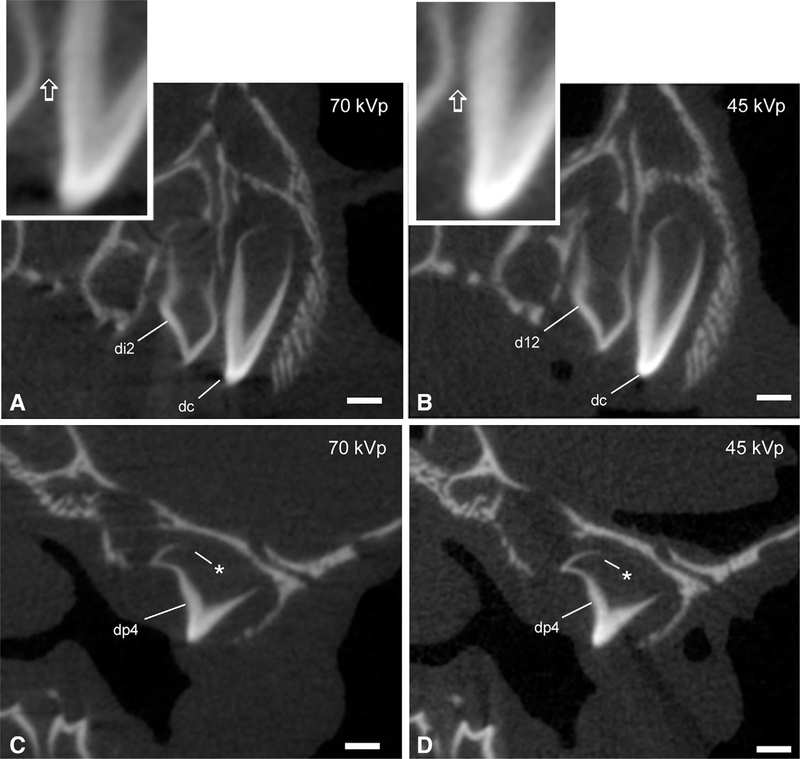

Description:Previous descriptive work on deciduous dentition of primates has focused disproportionately on great apes and humans. To address this bias in the literature, we studied 131 subadult nonhominoid specimens (including 110 newborns) describing deciduous tooth morphology and assessing maximum hydroxyapatite density (MHD). All specimens were CT scanned at 70 kVp and reconstructed at 20.5-39 μm voxels. Grayscale intensity from scans was converted to hydroxyapatite (HA) density (mg HA/cm| ) using a linear conversion of grayscale values to calibration standards of known HA density (R| = .99). Using Amira software, mineralized dental tissues were captured by segmenting the tooth cusps first and then capturing the remainder of the teeth at descending thresholds of gray levels. We assessed the relationship of MHD of selected teeth to cranial length using Pearson correlation coefficients. In monkeys, anterior teeth are more mineralized than postcanine teeth. In tarsiers and most lemurs and lorises, postcanine teeth are the most highly mineralized. This suggests that monkeys have a more prolonged process of dental mineralization that begins with incisors and canines, while mineralization of postcanine teeth is delayed. This may in part be a result of relatively late weaning in most anthropoid primates. Results also reveal that in lemurs and lorises, MHD of the mandibular first permanent molar (M| ) negatively correlates with cranial length. In contrast, the MHD of M| positively correlates with cranial length in monkeys. This supports the hypothesis that natural selection acts independently on dental growth as opposed to mineralization and indicates clear phylogenetic differences among primates.